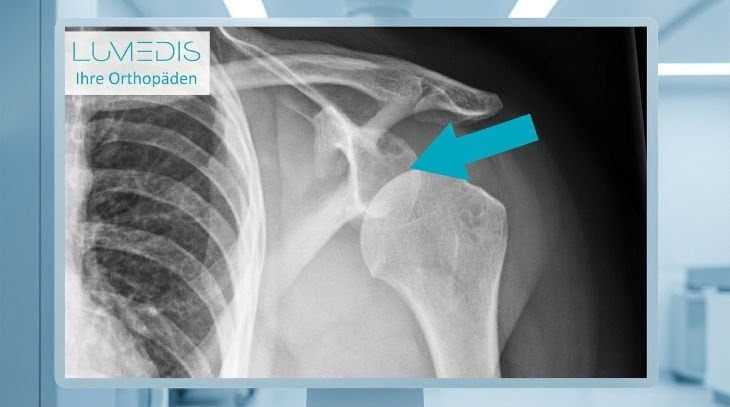

Röntgenbild rechte Schulter a.p.:

Röntgenbild linke Schulter a.p.: Oberarmkopfbruch (Oberarmkopffraktur)

Röntgenbild einer Tuberculum majus Abrissfraktur

Röntgenbild einer Tuberculum majus Fraktur rechts

Röntgenbild eines Bruchs des Tuberculum majus rechts